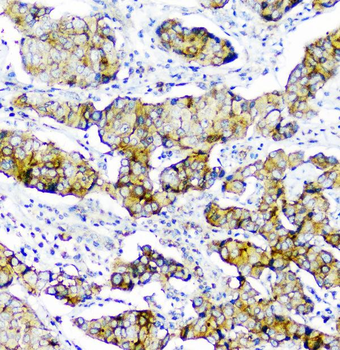

100 μg - PGP9.5 antibody [orb6713]Featured

ELISA, ICC, IF, IHC-P, WB

Human, Mouse, Rat

Rabbit

Polyclonal

Unconjugated